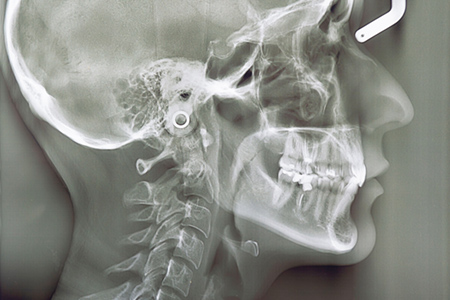

立体画像で診断や治療の精度を

高めています

当院では、精密な検査と診断を行うべく、歯科用CTやセファロといった専門的な機器を導入しました。歯や顎の骨の状態を立体的に撮影できるため、通常のレントゲンでは見つけにくい部分までしっかりと確認しやすくなります。こうした詳細な情報をもとに一人ひとりに合わせた治療計画を立て、より安心して治療を受けていただけるよう心がけています。

2 精密検査

お子さんのお口の状態をより詳しく把握するために、CTやセファロといったレントゲン機器を使用した撮影や、歯型採取などの検査を行い、顎の骨の成長具合や歯の位置関係をしっかりと確認します。